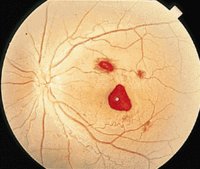

眼底出血

眼底出血不是一种独立的眼病,而是许多眼病和某些全身疾病所共有的特征。常见于高血压视

网膜病变、糖尿病及肾病引起的视网膜病变。视网膜静脉周围炎、视网膜静脉阻塞、视盘血管炎以及血液病引起视网膜病变,眼外伤性眼底出血。由于各种不同的病因导致相同的病理损害,如视网膜出血,渗出,微血管瘤、新生血管等。

(4)视网膜血管异常,各种不同的病因导致相同的病理损害,如视网膜出血、渗出、微血管瘤、新生血管等。

眼底出血的病理特征

主要以毛细血管病变最为常见,尤其是来自静脉方面的出血,多发生在患者出现局部或全身病变,由动脉方面发生的出血比较少见,主要由于毛细血管内膜损害,渗透性增加,使血液渗出,血液动力学的改变,

血液粘稠度高,静脉血流迟缓或滞留,静脉血栓,静脉壁的炎症等。动脉主要见于动脉血管壁局部粥样硬化或血管栓塞等情况。

特点:出血开始或有反复出血倾向,发病时间多在15天内,视网膜上点片状出血或以视乳头为中心,放射状出血,颜色鲜红。